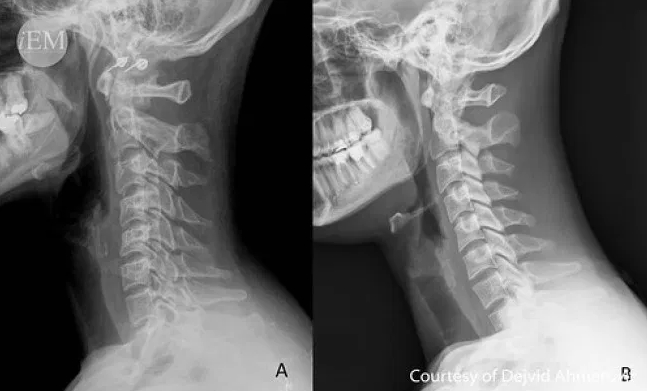

목디스크는 경추 뼈와 뼈 사이에 있는 물렁뼈 조직인 디스크가 어떠한 원인에 의해 탈출하여 신경을 눌러 통증을 일으키는 질환입니다. 일반적으로 목디스크는 퇴행성 변화에 의해 수핵의 탄력성이 떨어지면서 발생하는 경우가 많지만 최근에는 일상생활에서의 잘못된 자세습관에 의한 변형(거북목, 일자목), 운동 중 부상 등으로 발생하는 경우가 많습니다.